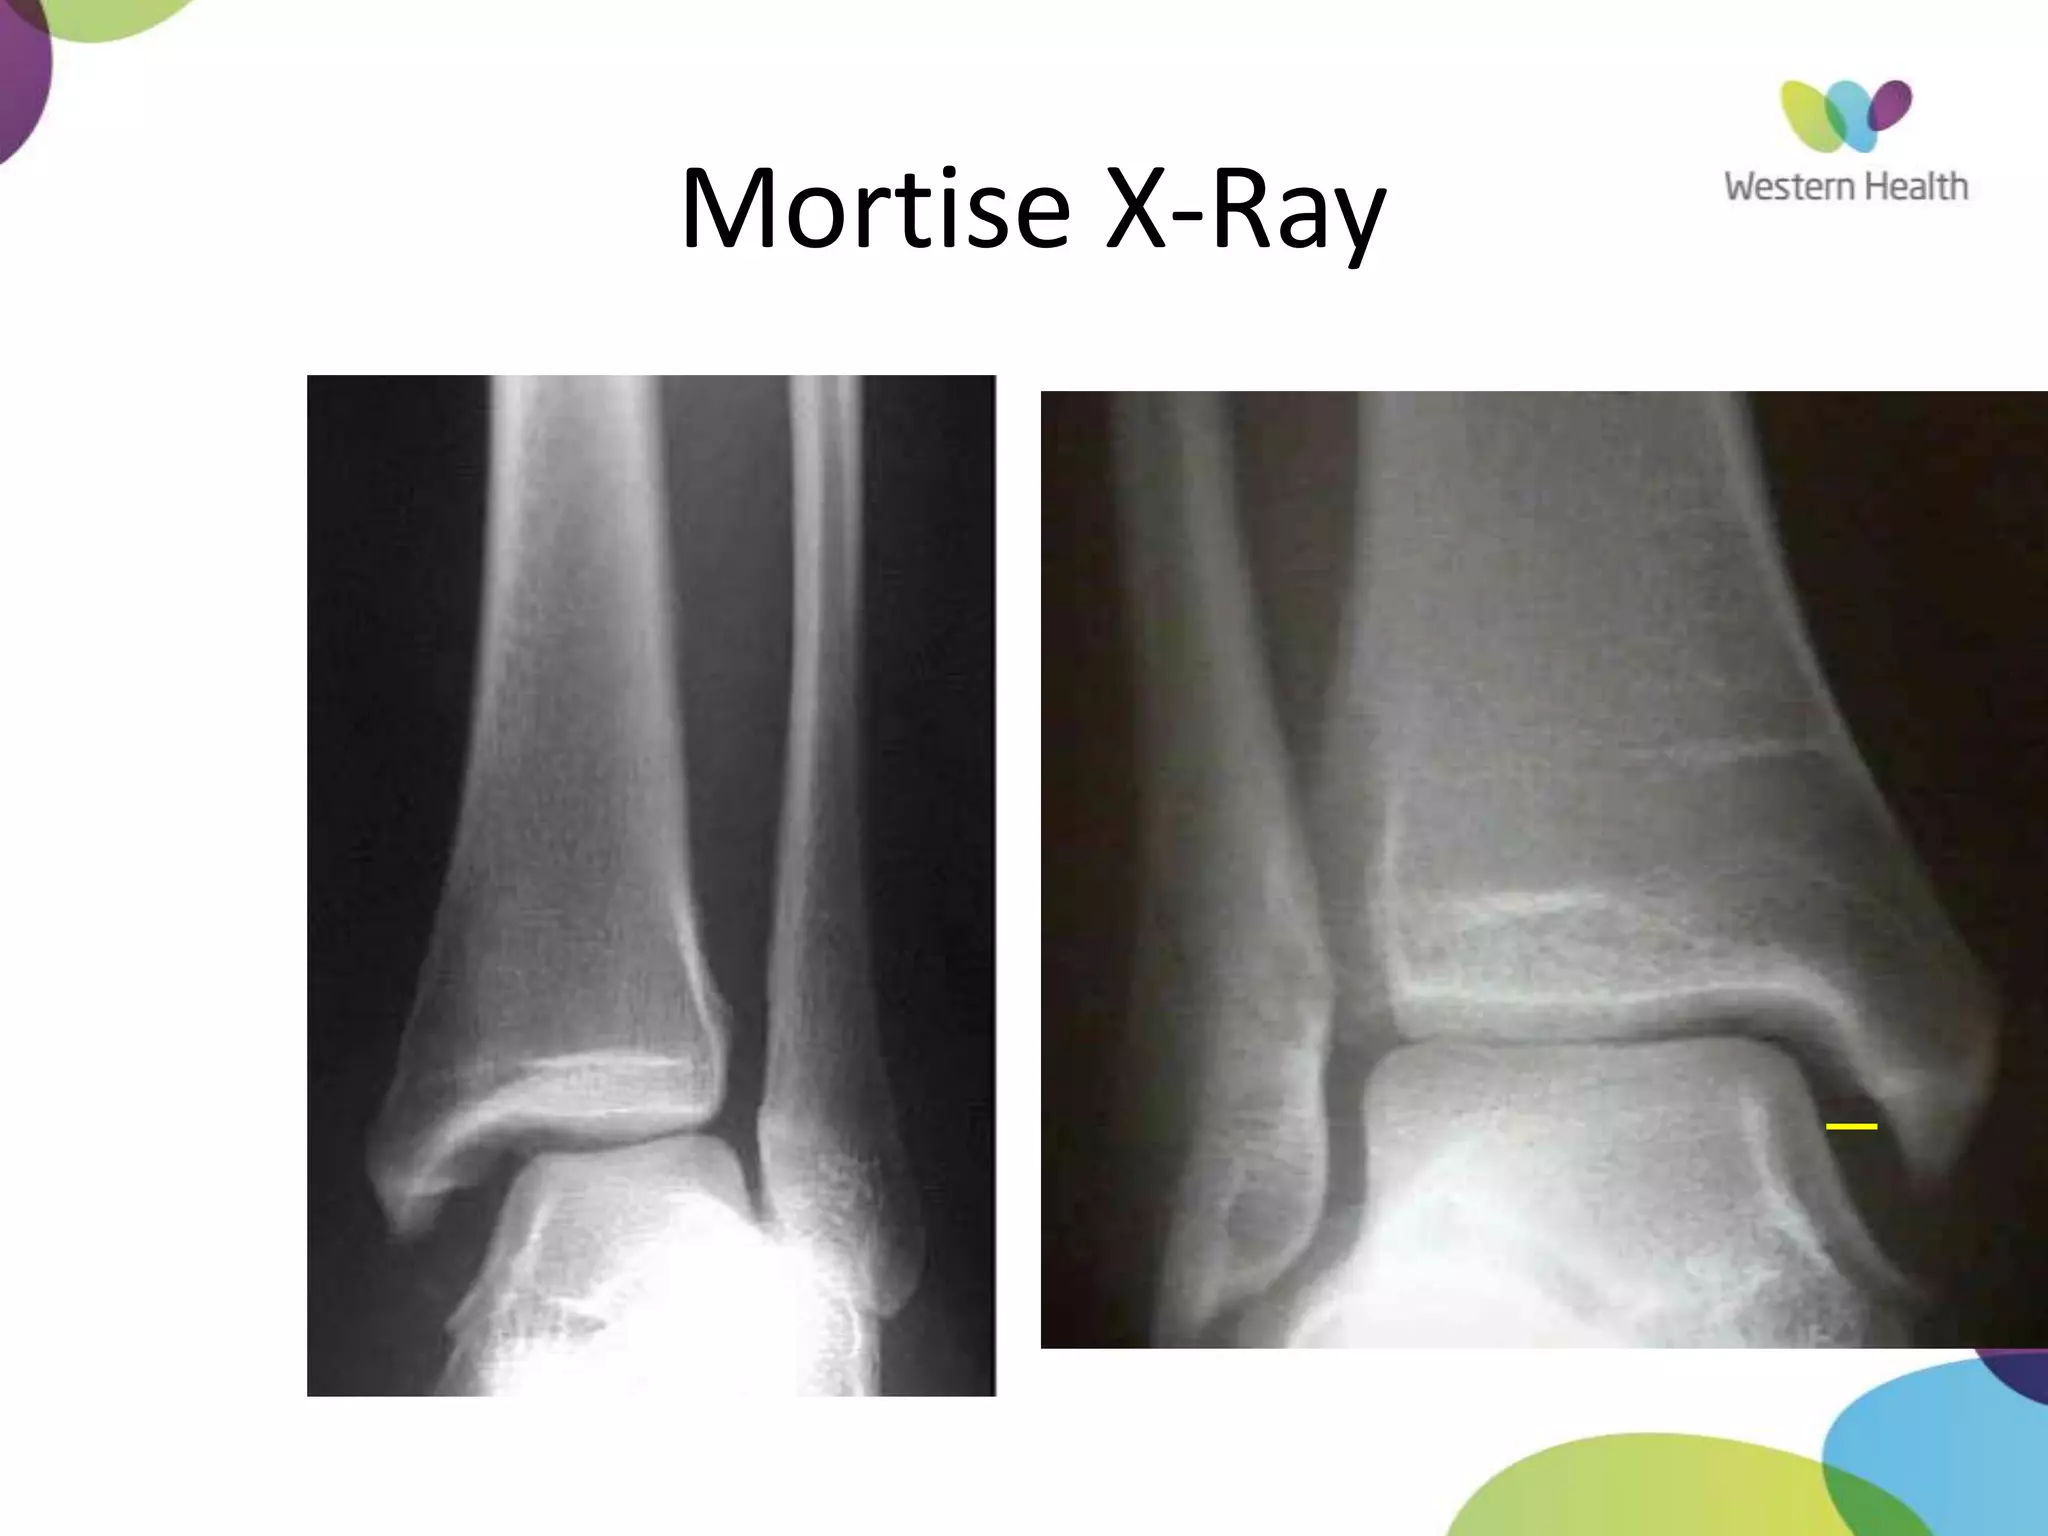

Mortise X-Ray

• ankle in 15-25° of IR

• Medial clear space

– Between lateral border of

medial malleous and medial

talus

– <4mm is normal

– >4mm suggests lateral shift

of talus